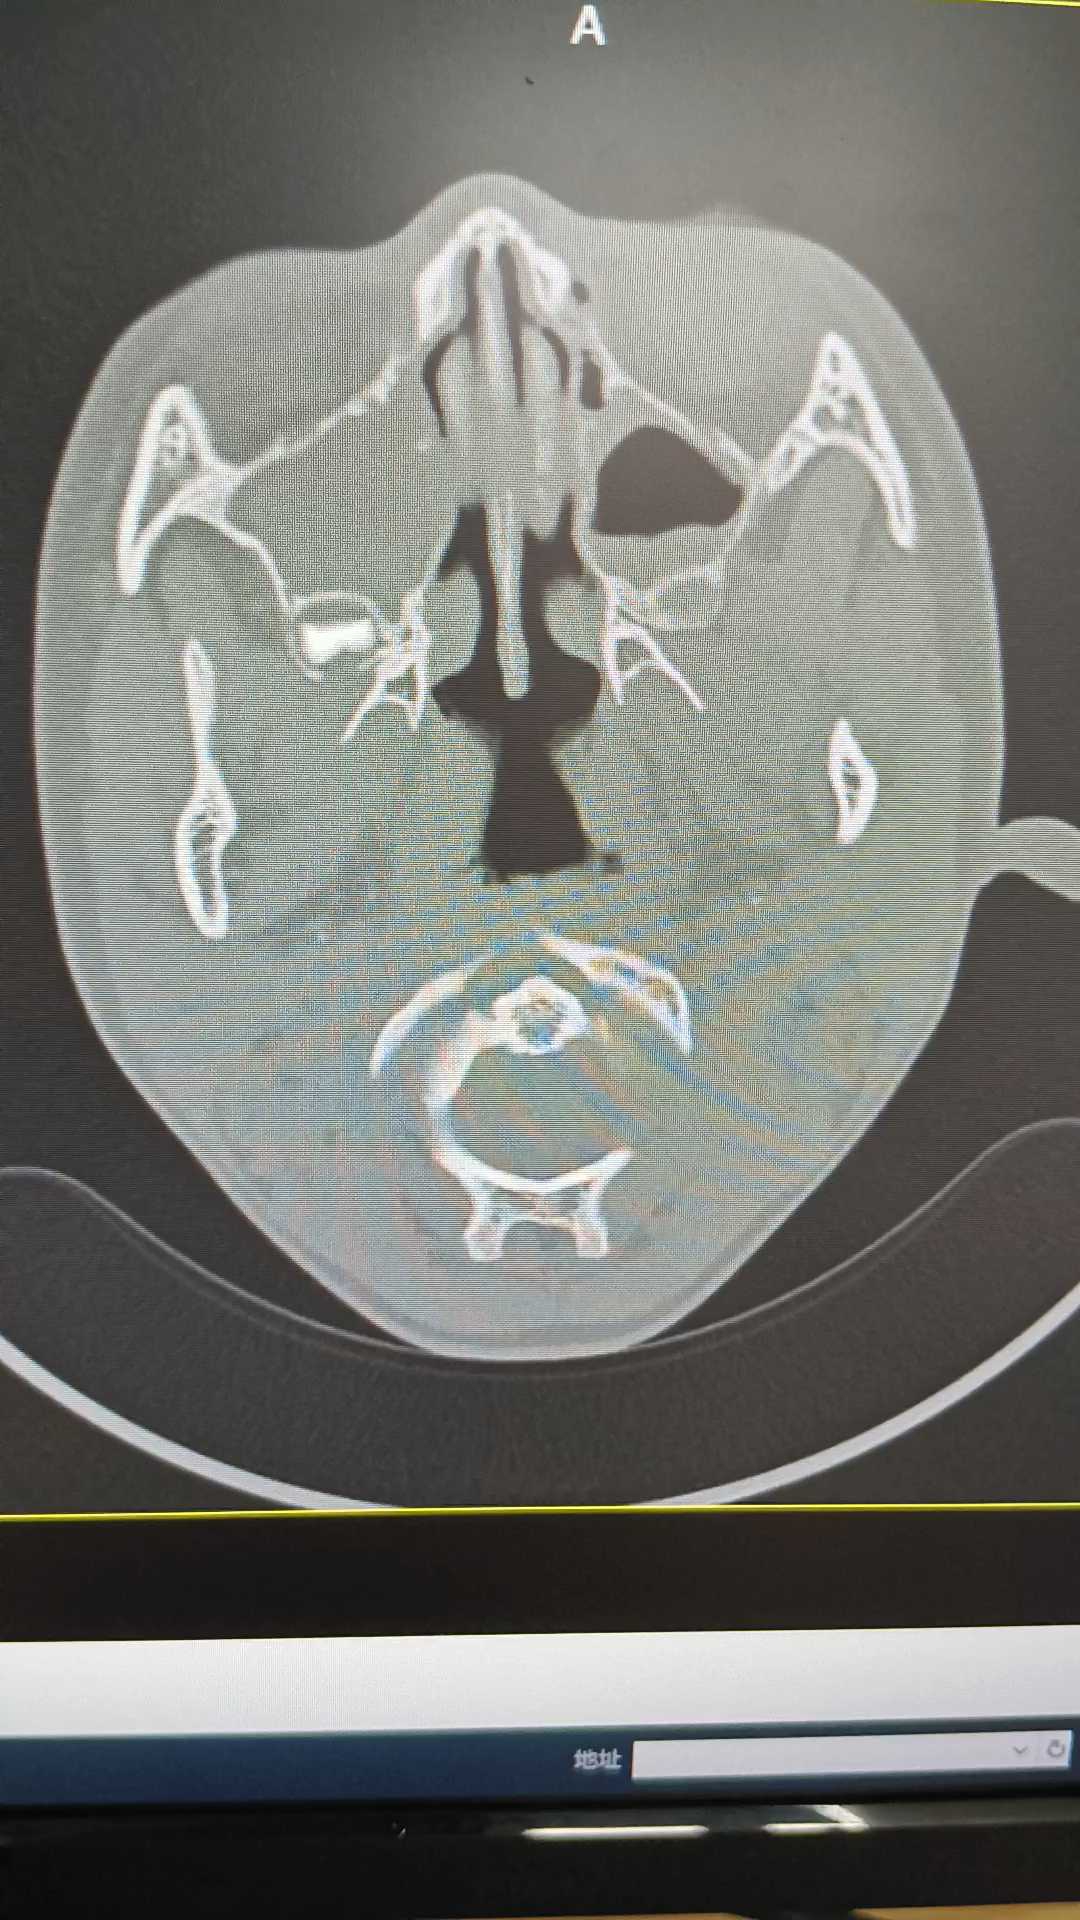

大前庭导水综合征+人工耳蜗植入术后影像CT如何查看!对耳聋相关的CT不是很懂,各位主任们,来讨论一下

CT报告

大前庭导水综合征如何确定?